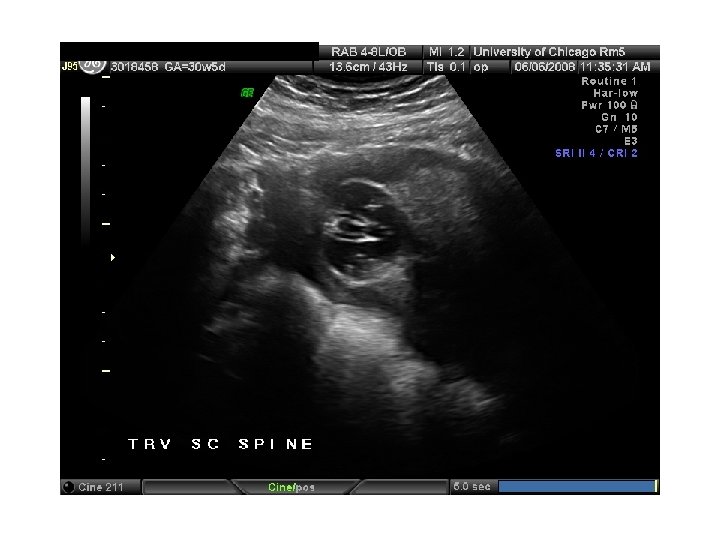

QUIZ What is Your Diagnosis? Case: Patient J. F. 30 years old, at 32 week gestation. Presented with the following pictures.

Answer: a) Trisomy 21 b) Non-immune Hydops c) Paravo virus Infection